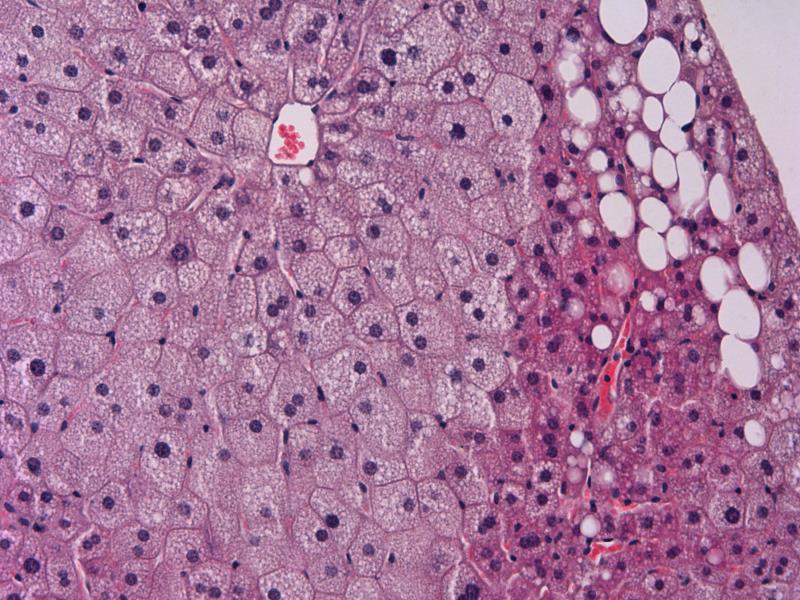

A long-acting FGF21* analogue, once-weekly efruxifermin, irrespective of dose, has been shown to reduce LFC (as per MRI-PDFF**) vs placebo at 12 weeks in F1–F3 NASH patients. [Hepatology 2020;72;1S;6A] Eighty participants were randomized 1:1:1:1 to receive either efruxifermin 28, 50, or 70 mg, or placebo. Of these, 68 had available MRI-PDFF assessments at baseline and week 12 (n=50 achieved ≥30-percent relative LFC reduction at week 12 [MRI-PDFF responders]). Forty-two of the MRI-PDFF responders comprised the Biopsy Analysis Set (BAS; those with baseline and post-treatment biopsies). [Nat Med 2021;doi:10.1038/s41591-021-01425-3]

Individuals with normalized LFC had a greater likelihood of achieving NASH resolution (odds ratio [OR], 4.08; p=0.0365) or NAFLD Activity Score (NAS) improvement by ≥4 (OR, 6.43; p=0.0068).

Of the 12 efruxifermin recipients included for histologic evaluation, four had fibrosis improvement (or reversal of cirrhosis) without NASH worsening, three achieved NASH resolution, while seven had NAS improvement by ≥2##. Of the five placebo-treated patients, only one achieved NAS improvement by ≥2##; none achieved the other two endpoints.